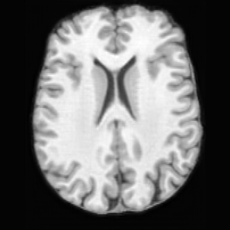

Healthy w/Lesion MaskPathologicalDifferencew/o LCGw/ LCG(a)Refer to captionRefer to captionRefer to captionRefer to captionRefer to captionRefer to captionHealthy w/Lesion MaskPathologicalDifferencew/o LCGw/ LCG(b)Refer to captionRefer to captionRefer to captionRefer to captionRefer to captionRefer to caption

Figure 7: Ablation study of Lesion Consistency Guidance (LCG). Without LCG, the generated pathological regions are indistinct and show weak pathological expression in both examples.

Lesion Consistency Guidance. Fig. 7 illustrates the impact of Lesion Consistency Guidance (LCG) for healthy-to-pathology editing. Without LCG, the generated lesion regions appear blurry around lesion boundaries, and the pathological patterns are less distinct, resulting in ambiguous lesion localization and weak pathological expression. Incorporating LCG produces lesions with more precise localization and well-defined shapes that better align with the given lesion masks, as well as textures and contrasts that exhibit stronger pathological characteristics. These results demonstrate that LCG effectively enforces lesion-aware conditioning, enhancing both spatial and semantic consistency of the generated pathological regions.